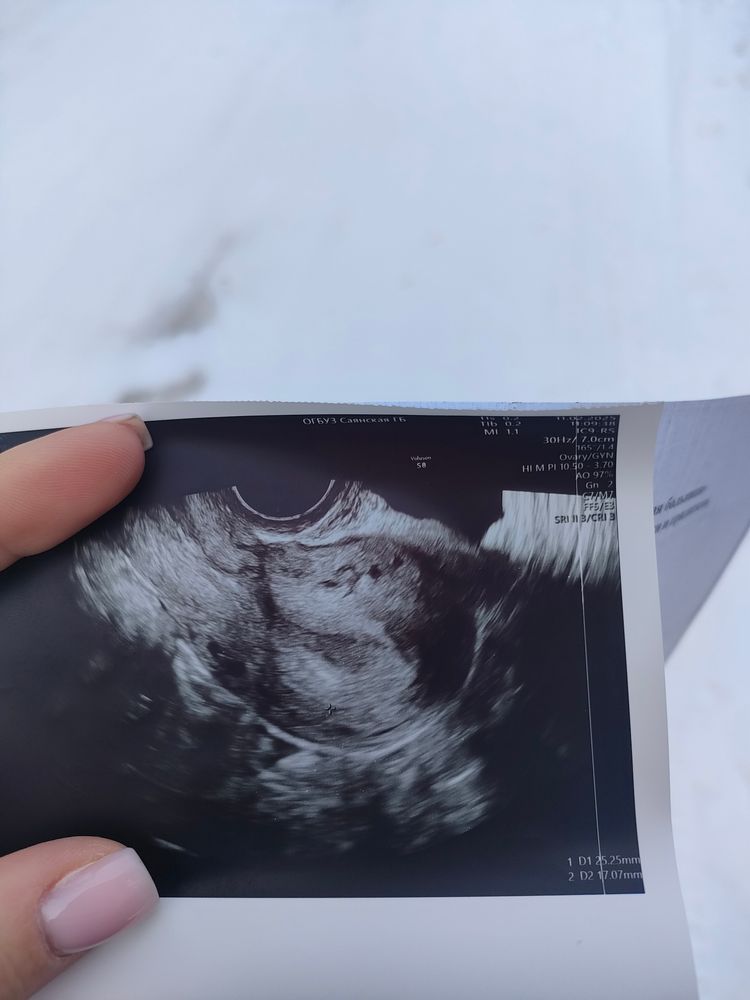

здравствуйте , ну всю себя съем за 2 недели ожидания, может тут кто что подскажет. 5 положительных тестов на беременность, месячные должны начаться завтра, пришла сегодня на узи, а мне врач сказала, что срок ещё совсем маленький, может не увидеть ничего, даже смотреть не будет. я ее уговорила, т. к. узи платное, по итогу "достоверных данных за беременность на момент осмотра нет", говорит через 2 недели приходи, но тем не менее выкатила мне снимок, весь инет по картинкам обшарила, вроде как есть, да еще и не одно... теперь поедаю себя ещё хлеще. фото прикреплю

редакт: а что за точки на снимке? 🥲😳